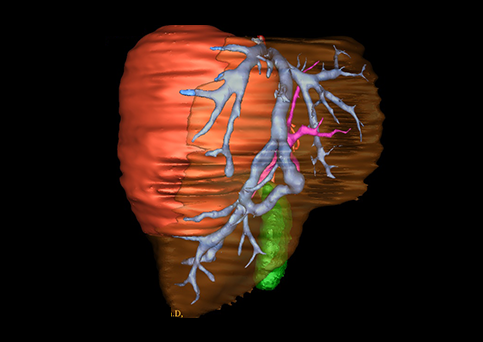

近年来由于数字医学的发展,基于可视化三维重建技术的计算机辅助手术系统极大推进了小儿肝脏肿瘤的精准手术的进步。可以立体透视肝脏解剖、精确掌握肝段的边界、精确测算肝段乃至任意血管所支配的功能体积、准确定位病灶及其与邻近血管的解剖关系,最终对不同手术方案进行比较、筛选和优化。因此,计算机辅助手术规划系统是实现精准肝切除的有力辅助工具,是未来数字外科、精准外科等21世纪外科新理念的重要技术支撑。

计算机辅助手术规划系统具有良好的操作可行性、计算准确性和三维显示效果,可半透明、交互式显示真实的肝内立体解剖关系和空间管道变异,准确计算肝内管道的直径、走行角度,两点间的垂直距离,和任意血管的支配或引流范围等传统二维影像无法获取的信息,有助于实施个体化手术,提高了手术的确定性、预见性和可控性。计算机辅助手术规划系统可直观显示预留肝脏的结构和功能,并可通过虚拟切割功能辅助术者对手术方案进行蹄选和优化,系统评估手术风险和制定对策,改变了部分二维规划的术式和切除范围,使部分二维规划认为不能切除的患者成功手术,提高了手术的根治性、安全性和病变的可切除性,更加符合精准肝脏外科的术前规划要求。详见第11章。

随着计算机技术及影像检查技术的不断发展,以精确的术前影像学和功能评估、精细的手术操作为核心的精准肝切除技术日益受到重视。基于数字医学的计算机辅助手术技术(computer-assisted surgery,CAS)则是实现肝脏精准手术操作的基础。计算机辅助手术系统(CAS)可将术前二维(two dimensional,2D)的CT/MRI影像数据进行三维(three dimensional,3D)重建,建立个体化的肝脏三维解剖模型,清晰显示肝脏内脉管系统的走行及解剖关系,还原病灶与其周围脉管结构的立体解剖构象,准确地对病变进行定位、定性和评估,制定合理、定量的手术方案,实施个体化的肝脏血管取舍分配方案及实施精准肝脏手术。一般认为CAS包括:创建虚拟的患者的图像;患者图像的分析与深度处理;诊断、手术前规划、手术步骤的模拟;术中实时导航。应用本技术后,由于可以更清晰地看出肿瘤的界限,特别是根据肝血管的显影,判断出肿瘤与门静脉及肝静脉的关系以在手术前较准确地估计出手术成功切除的可行性。以往部分根据普通强化CT判断无法手术的病例而被评估为可以成功切除并手术成功。